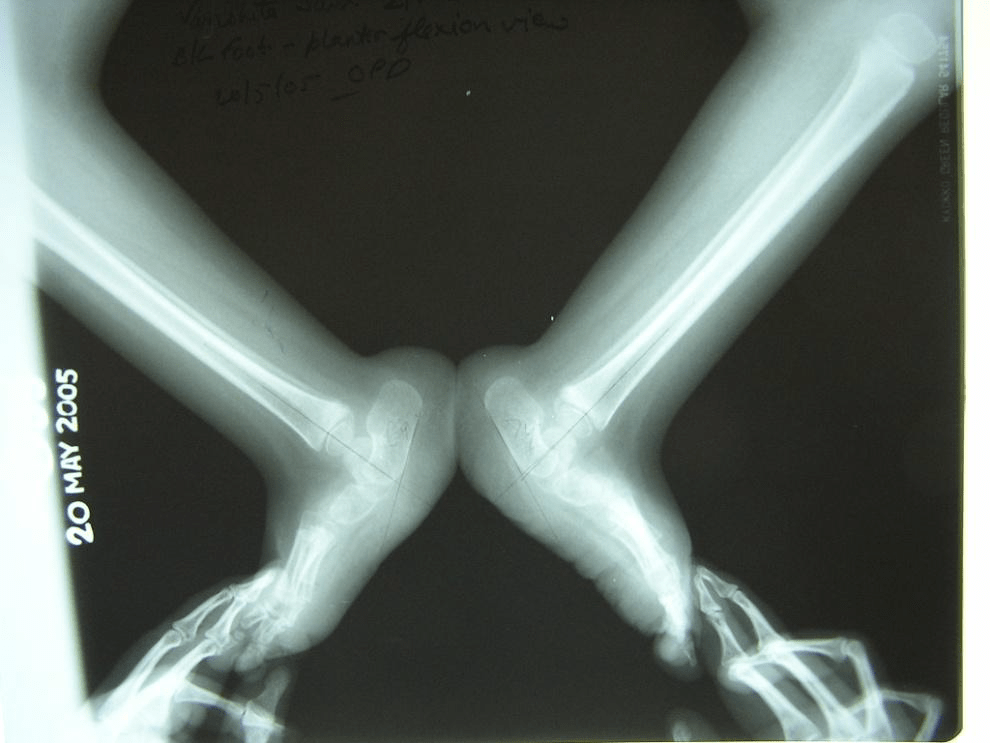

Figure 3 : (top) Lateral views showing ‘vertical talus’ with talo-navicular dislocations on both sides. (bottom) Forced plantar flexion views do not show any change in the talo-calcaneo-navicular relationship.